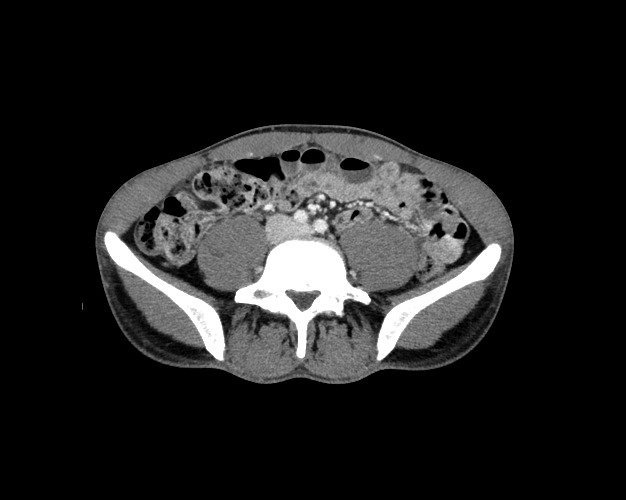

Body

Covers abdominal CT anatomy.